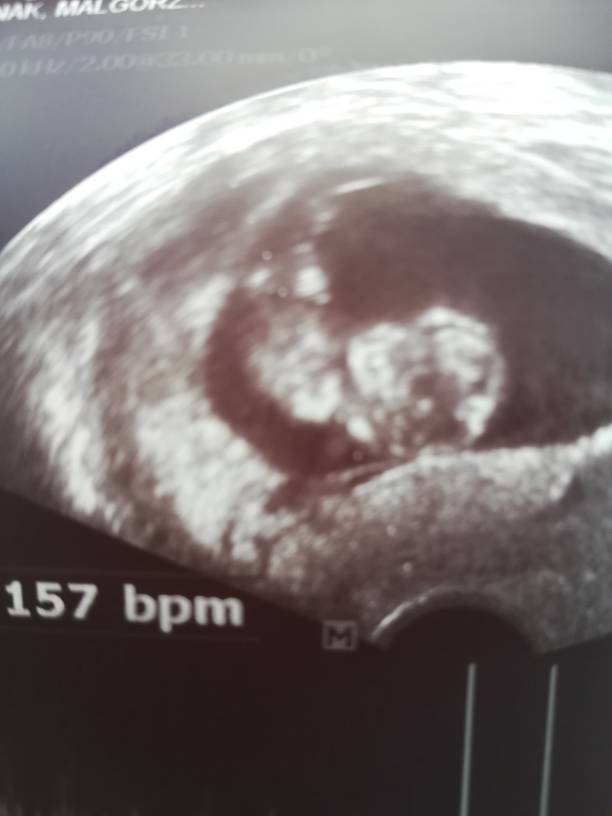

To bylo drugie poronienie pierwsza ciaza tez poronienie w 7 tyg.serduszka zawsze przestaja bic. Tez odwiedzilam Pasnika i mam cala liste wiec wierze ze teraz sie uda[emoji16] crio w polowie lipca. Ps.jedziemy na 1 wozku[emoji16]